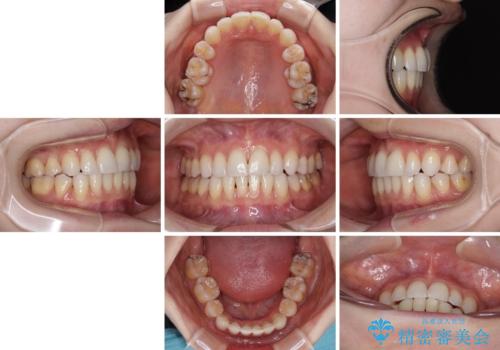

アンカースクリューを用いて正中位置を調整したことで、上下の正中位置をほぼ一致させることができました。

移動量が多かったため、治療期間は長くなりましたが、大変満足のいく仕上がりとなりました。